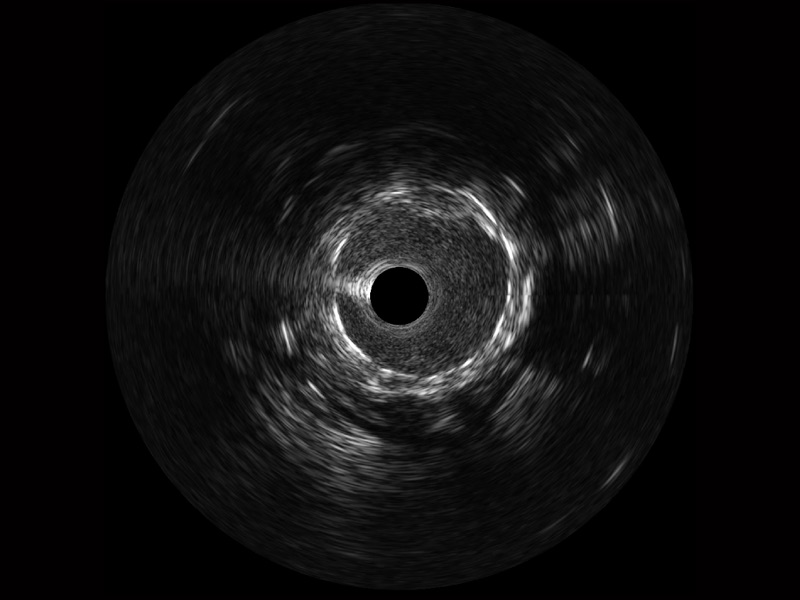

百老汇电子游戏官网宽频IVUS图像

传统IVUS图像

对比传统IVUS导管成像,百老汇电子游戏官网宽频IVUS图像的近场支架梁显影更细腻,远场中膜外血管仍清晰可辨,兼顾远中近,兼顾分辨力与穿透深度